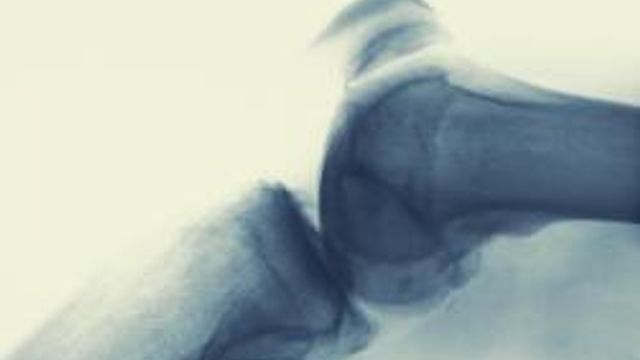

Dopo il gomito del tennista e il ginocchio della lavandaia, l'epoca 2.0 porta con sé un malanno per le giunture legato alle nuove abitudini di vita. Si tratta del "ginocchio da scrivania" che condanna i forzati della sedia a dolori e rigidità articolari.

Secondo gli esperti, negli ultimi dieci anni c'è stata un'impennata di questa malattia anche a causa dell'uso sempre più pervasivo del pc. La routine lavorativa, infatti, costringe molti a rimanere con le ginocchia nella stessa posizione per troppo tempo.

Un danno per le articolazioni che, come aggiunge il medico: "sono fatte per stare in movimento e se noi le facciamo stare troppo a riposo cominciano a soffrire". In particolare, il ginocchio "risente di più di quest'immobilità forzata: è infatti un'articolazione nata per essere mobile e fluida. Purtroppo la vita sedentaria rende il nostro ginocchio sempre più rigido".

Quando il corpo si abitua a sessioni sulla sedia di otto ore al giorno il corpo ne risente. Rossetti spiega le fasi del processo: "Diminuisce la produzione di liquido sinoviale che lubrifica l'articolazione del ginocchio e distribuisce nutrimento alle cellule cartilaginee che ricoprono la superficie articolare. Arrivano i primi disturbi, il ginocchio fa male e non si riesce a stenderlo bene. Poi c'è il problema dell'aumento del peso che arriva inevitabilmente se si sta troppo fermi. Se non si corre ai ripari, dimagrendo per esempio, si può rimanere vittima di un danno articolare con sofferenza della cellula cartilaginea. Tutto ciò favorisce la comparsa di lesioni artrosiche. Da qui non c'è scampo: si passa direttamente alla chirurgia ortopedica".